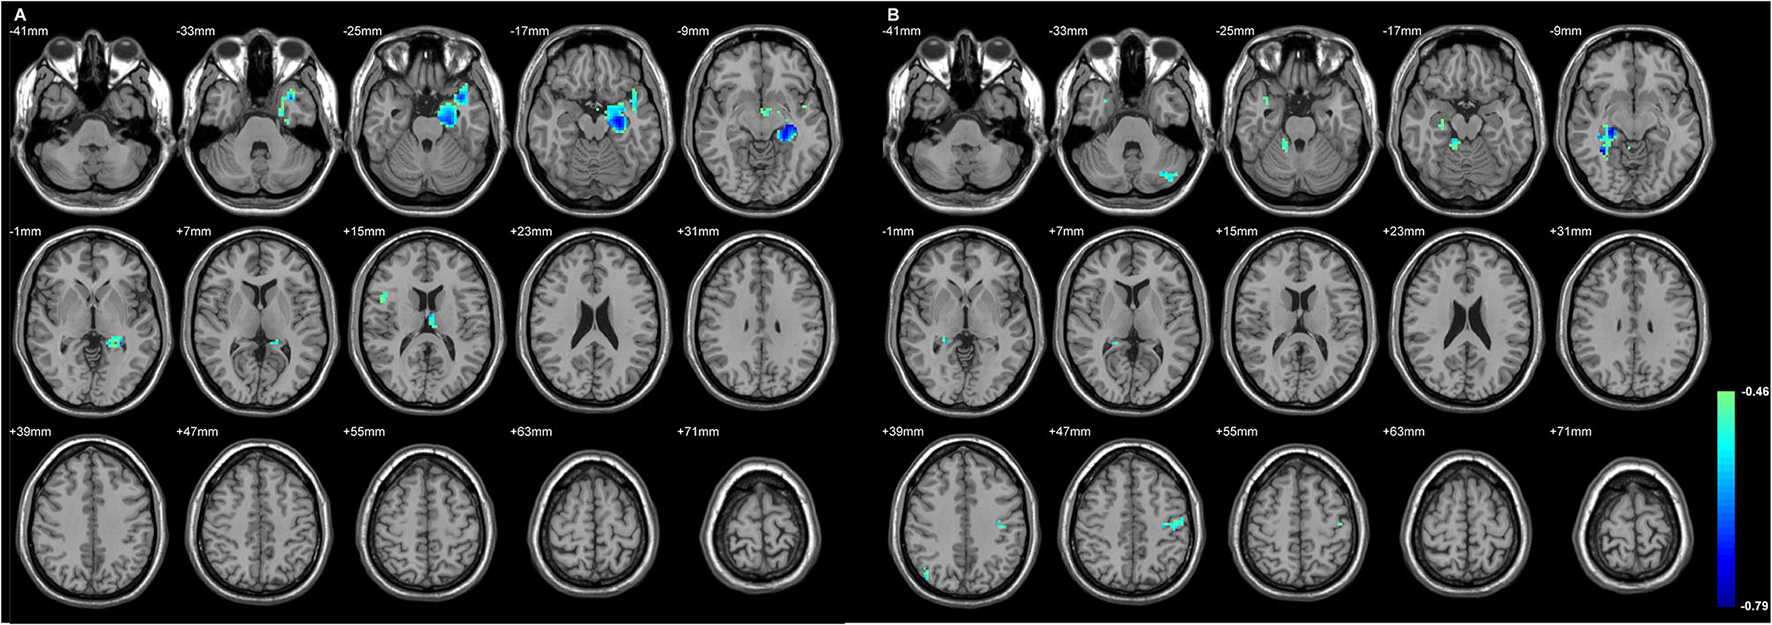

The Status of the Volume Loss of Both Sides of Thalamic Subfield Was Primarily Related to the Ipsilateral Inferior Frontal GMD Changes

Figures 4, 5 exhibited that the distribution of the neocortical atrophy was strongly associated with the amount of the sum of volume loss of the thalamic subfields on each side. GMD of the ipsilateral inferior frontal gyrus was positively related to each side of thalamic subfield volume changes in L-TLE. Meanwhile, it was negatively correlated with the volume loss of each side of thalamic subfields in R-TLE. In addition to the thalamus, GMD of the left caudate nucleus was another deep structure that was related to the thalamic subfield volume changes in L-TLE (Table 6).

Figure 4

The regions with their GMD related to the (A) left AV-LD-LP- CeM-CL-MV(Re) volume loss and the (B) right LD-MV(Re) volume loss in L-TLE. All depicted regions showed a positive relationship, and were mostly located in the left frontal and temporal lobes. GMD of the left inferior frontal gyrus was positively related to each side of thalamic subfield volume changes in L-TLE. Differences with a p < 0.01 were considered significant (with a threshold p < 0.01 and a minimum cluster size = 354 voxels, as determined by the AlphaSim correction).